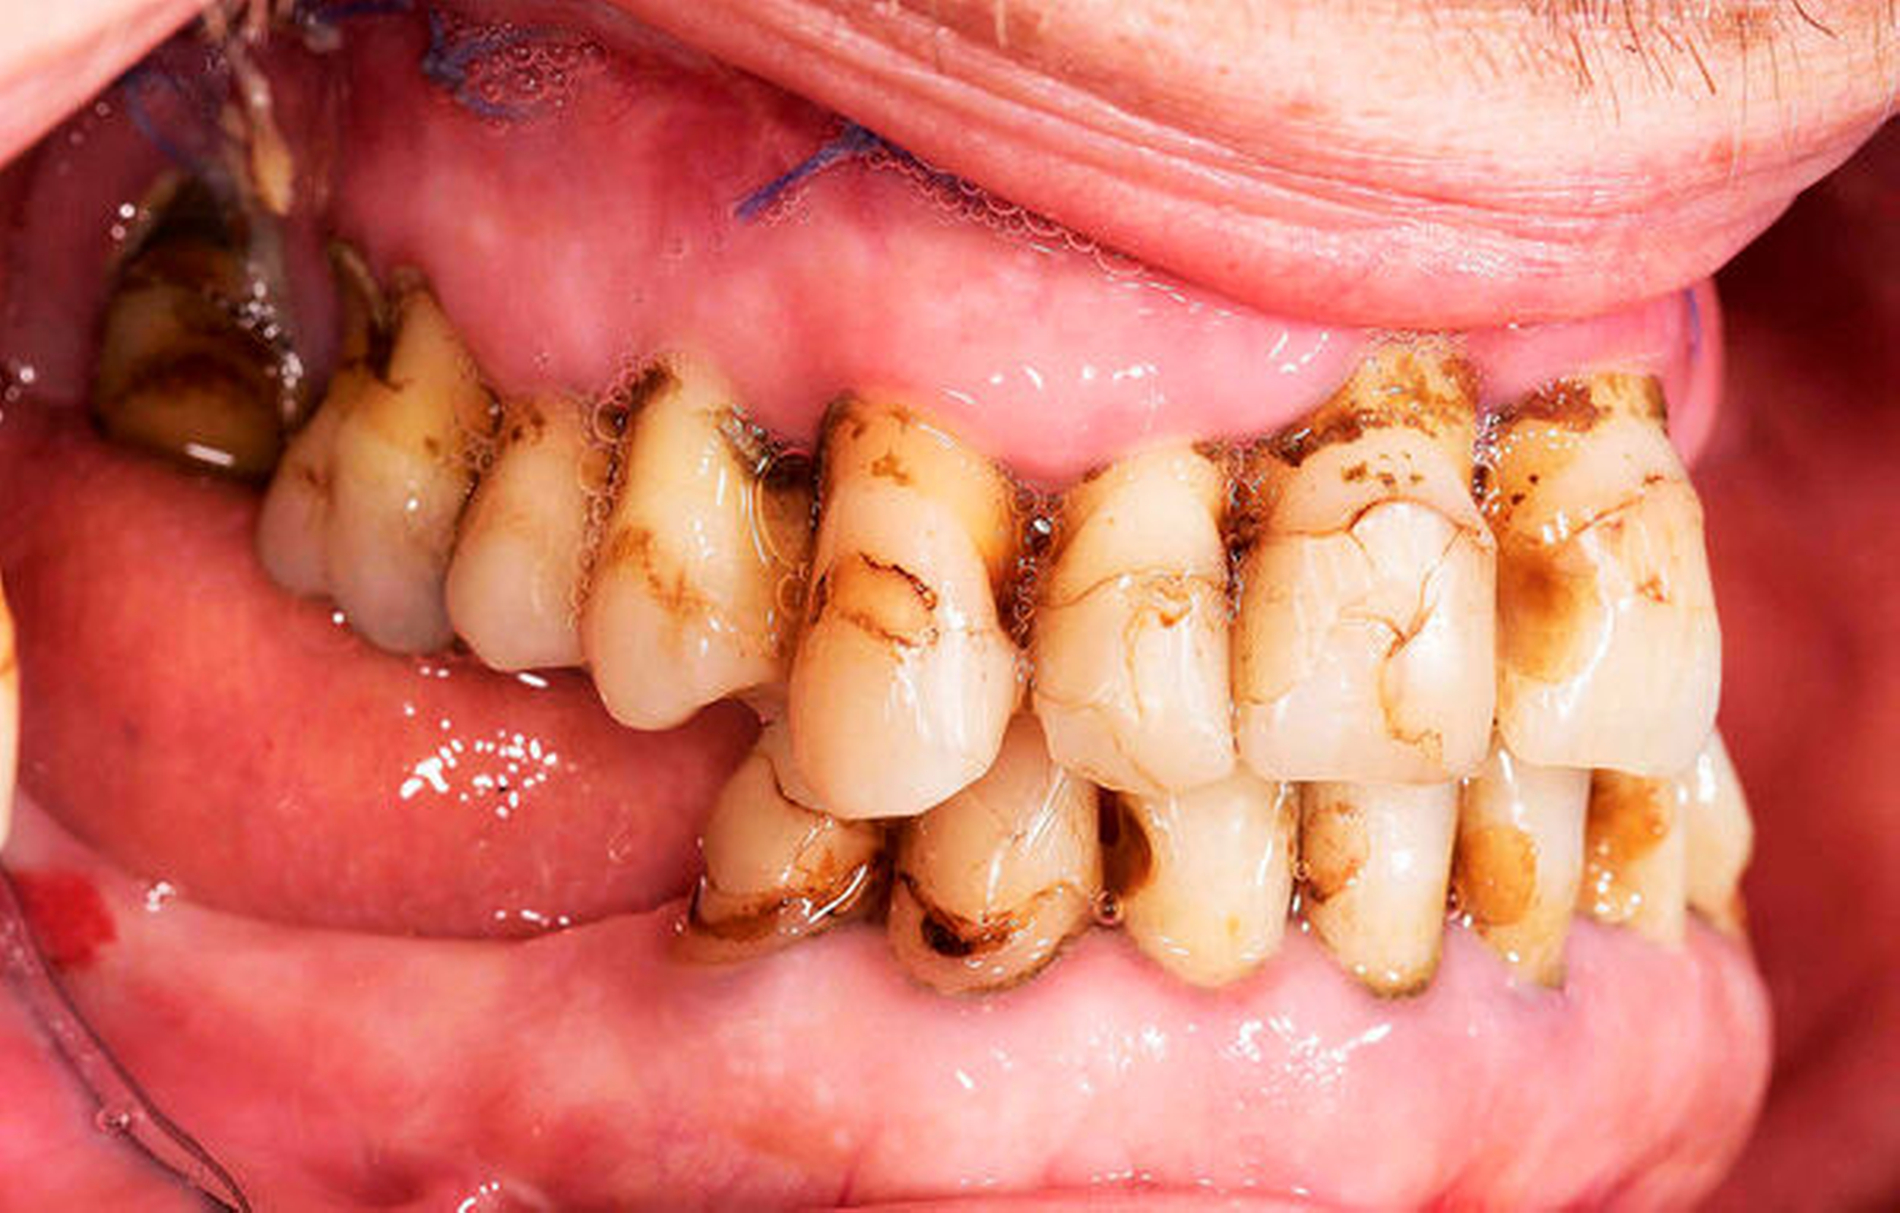

Bei der ersten Vorstellung in der Dysgnathie-Sprechstunde imponierte eine 10 mm große, umgekehrte, sagittale Frontzahnstufe. Die Mittellinie des Unterkiefers wich um 4 mm nach rechts ab. Die Zähne des teilbezahnten Ober- und Unterkiefers hatten jeglichen Kontakt verloren (Abbildungen 5 und 7).

Die unverhältnismäßig große Zunge zeigte dentale Impressionen. Nach Festlegung des Zielbisses in Abstimmung mit den Kollegen der Prothetik erfolgte eine bimaxilläre Umstellungsosteotomie mit Vorverlagerung des Oberkiefers um 8 mm nach LeFort-I-Osteotomie und Rückverlagerung des Unterkiefers nach sagittaler retromolarer Osteotomie (Abbildungen 6 und 8). Im gleichen Zug wurde eine Zungenreduktionsplastik nach Rheinwald [Egyedi et al., 1964] durchgeführt.